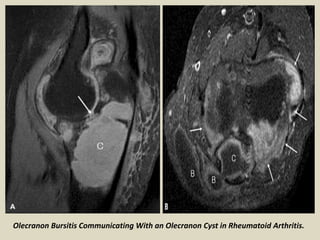

Olecranon Bursitis Communicating With an Olecranon Cyst in Rheumatoid Arthritis.